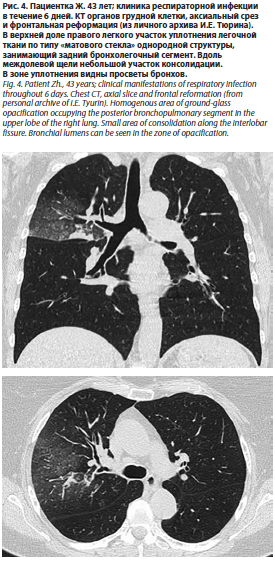

Что же касается результатов КТ, то они, также не являясь строго специфичными, могут оказать дополнительную помощь при обнаружении таких рентгенологических находок, как участки «матового стекла», утолщение стенок бронхов/бронхиол, цетрилобулярные очаги (рис. 4, 5).